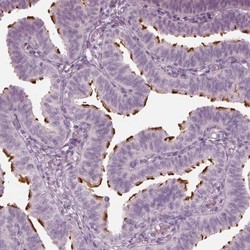

- Main image

- Experimental details

- Immunohistochemistry-Paraffin: FAM154B Antibody [NBP1-90521] - Staining of human fallopian tube shows strong positivity in cilia of glandular cells.